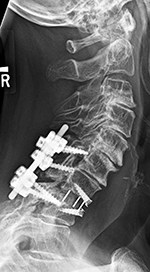

Cervical spine anterior and posterior fusion |

Odontoid screw (nail) fracture fixation with posterior cervical fixation plates and screws |

Young woman with traumatic locked facets at C6-7 and C7 body fracture. A posterior cervical fusion with lateral mass screws (cervical spine) and pedicle screws (thoracic spine) and rods extends from C4 to T2. There is an anterior cervical fusion plate and screws at C6-7 with a intervertebral disk cage at C6-7 and a crosslink at C6. |

| There is also an anterior cervical fusion plate and screws from C3-6. |